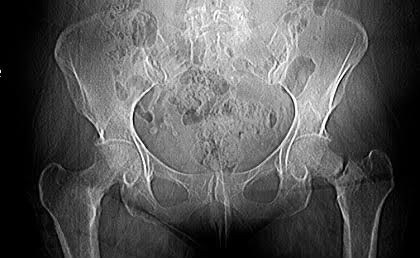

Mi abuela tiene 73 años y siempre ha sido una mujer increíblemente independiente. Es madre de cinco, y quienes la conocemos sabemos que nunca ha querido ser una carga para nadie; disfruta hacer sus cosas sola, salir, moverse y mantenerse activa. Lamentablemente, hace poco sufrió una fractura que ha complicado gravemente su movilidad, y los médicos han determinado que necesita un reemplazo de cadera y de rodilla para poder recuperar su calidad de vida.

La cirugía es urgente y el costo supera por mucho lo que nuestra familia puede cubrir. Por eso, con todo el amor del mundo, estoy abriendo este GoFundMe para ayudarla a recibir la operación que necesita y volver a caminar sin dolor.